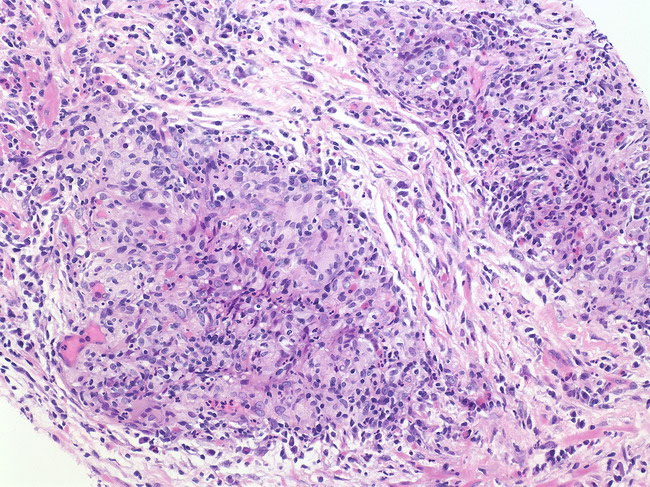

Gleason Pattern 3

Has variably sized glands that are well formed

- the glands are discrete units (should be able to mentally draw a circle around well-formed individual glands)

- should be able to assign Gleason grade at low power

- Gleason 3 are either: infiltrative bwt b9 glands, more variably sized or smaller than Gleason 1 and 2